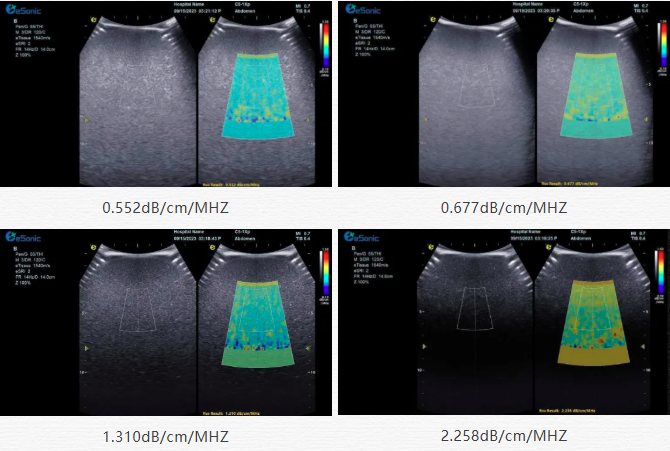

该技术基于声波在介质传播时的衰减,衰减由声吸收、反射、散射及波束扩散所致,声衰减系数(α,单位 dB/cm?MHz,与超声频率和传播距离成正比)可通过测定同频超声波在组织中的衰减程度,借回波信号分析预测声衰减系数或衰减率来评估组织特性。

声衰减定量成像(ATI)| 无创检测领域的革新之光(图2)

目前市面常用瞬时弹性成像或仿体参照法,存在适用性、准确性差及无衰减图局限。新航娱乐则采用准确度更高的 ALA 幅度损失衰减法,超声波深度传播时回波幅度渐降,其对数与深度有良好线性关系,声衰减量与传播衰减系数成函数关系,调节取样框大小位置可实时得样框内组织衰减系数,用于定量评估病变程度。